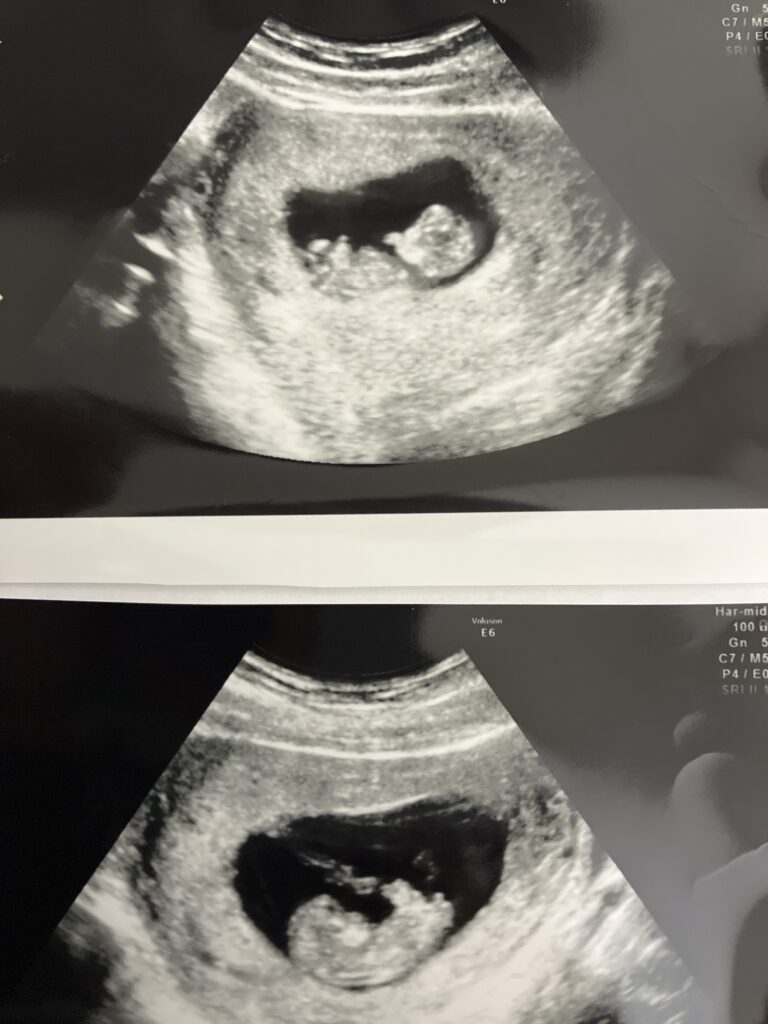

前回はまだ双子の可能性が高いという内容だったから、先生に

私「双子じゃないとしたら、このもう一つの丸いのは何ですか?」

先生「うん、血の塊やね」

という事を聞いてましたが、2度目の診察を終えて

先生「うん、やっぱ双子やね!この前の子が帰ってきてくれたのかもしれんねー😊」

と、看護師さんもニコニコ。

私も、その言葉を聞いてからなんだかようやく腑に落ちた気がして、やっと喜べたのを覚えてます😌